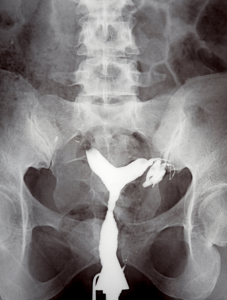

Figure 2: X-ray image of uterus